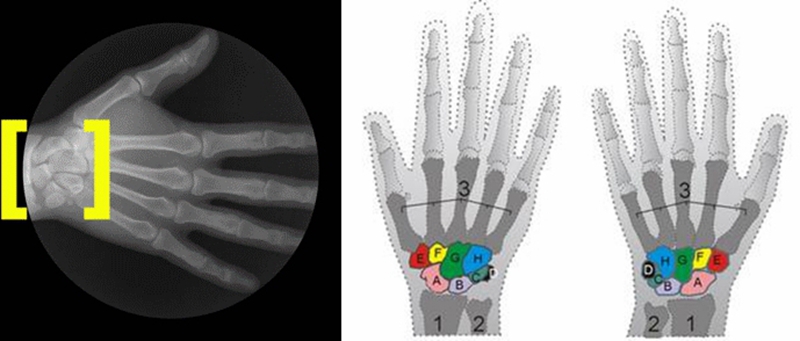

腕关节是人体重要的关节之一,具有复杂的骨、软骨及韧带结构。手腕是由桡骨(radius)、尺骨(ulna)、八块腕骨(carpal bones)、27 条韧带(ligaments)以及三角纤维软骨复合体(TFCC)所组成。

其中包括三个关节面: 远端桡尺关节(distal radioulnar joint, DRUJ),桡腕关节(radiocarpal joint)和腕中关节(midcarpal joint)。

腕关节解剖